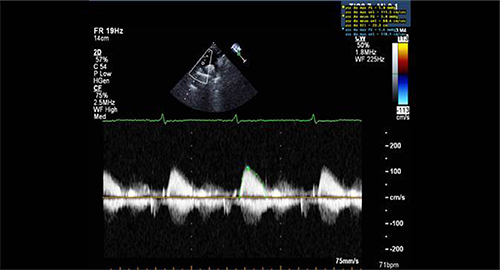

Figure 3: Sample of Doppler image and measurements obtained from apical window in a control patient.